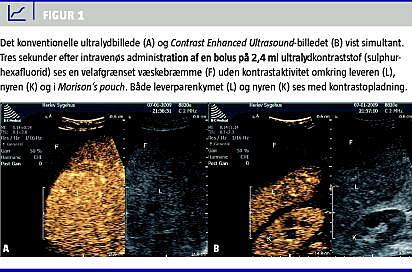

For at undersøge det nærmere blev der foretaget CEUS. I en i forvejen anlagt intravenøs adgang blev der givet en bolus på 2,4 ml ultralydkontraststof (sulphurhexafluorid) efterfulgt af 10 ml isotonisk saltvand. Det konventionelle UL-billedet blev vist simultant med CEUS-billedet på ultralydskannerens skærm. CEUS viste en velafgrænset bræmme uden kontrastaktivitet omkring leveren, i Morison's pouch og mellem tarmene (Figur 1 ).

Ved CEUS blev der påvist et betydeligt større volumen fri væske i abdomen end først anslået ved FAST. Ved CEUS blev det vurderet, at der var mere end to liter frisk blødning i abdomen. Ved hjælp af CEUS påviste man også den sandsynlige blødningskilde i form af en overfladisk laceration på leveren ud for biopsiindstiksstedet. Der blev foretaget akut laparotomi, som viste 4.500 ml hæmoperitoneum og en overfladisk laceration af leveren i segment VI og VII.